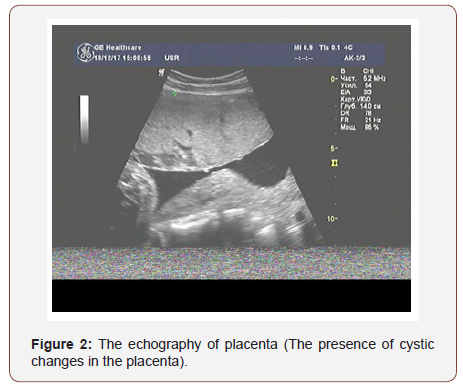

The results of ultrasound examination showed a single fetus in the uterus in the transverse position; in terms of its photometric parameters, the fetus fitted 31 weeks of gestation, the expectable estimated fetal weight was 1400 grams., a very thick placenta - up to 86mm (Figure 1) with medium echogenicity, multiple small anechoic structures (Figure 2), moderately expressed oligohydramnios (amniotic fluid index - 72mm) and a short neck uterus according to the results of cervicometry (20mm). Another feature is large, multichamber, an echogenic, bulky ovarian formations on both sides of the uterus (Figures 3&4). The size of the right ovary was 88 × 53 × 83mm, of the left one - 91 × 56 × 82mm. Hemodynamic disorders of the uteroplacental circulation were not detected.

Considering the data of ultrasonic examination of the fetoplacental complex and the revealed pathological changes, we noticed the signs of a trophoblastic disease (thick, swollen, cysticaltered placenta and echo graphic changes in the ovaries that indicate the presence of theca lutein cysts).